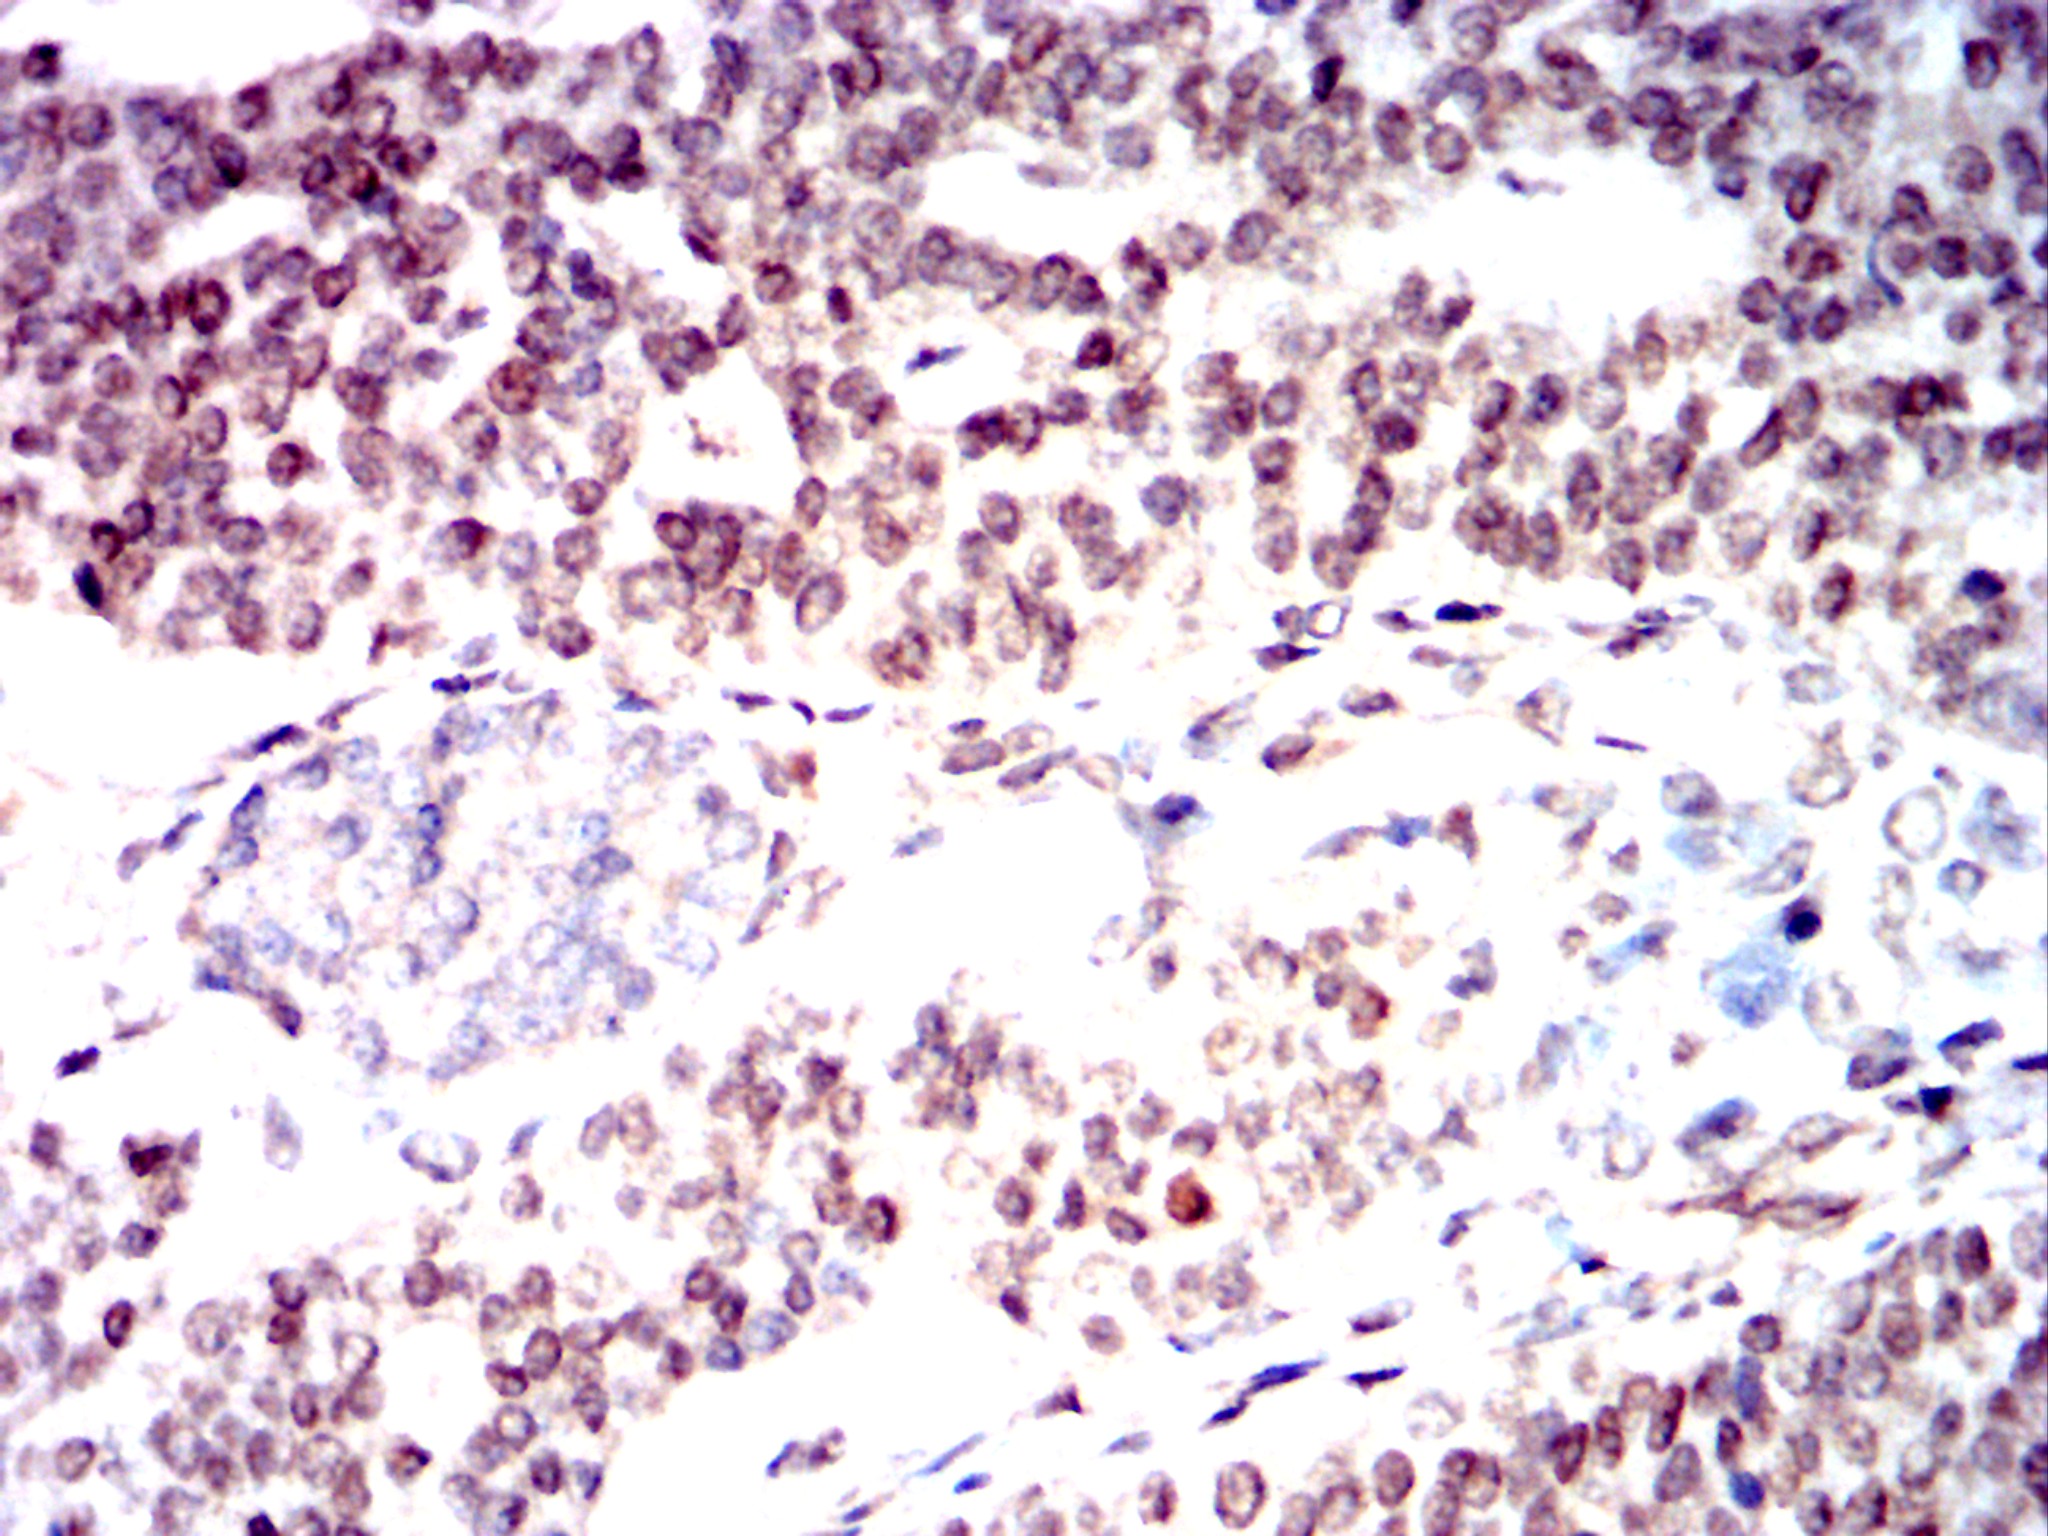

分类: 科研抗体货号: 32439别名: AT1; ATA; ATC; ATD; ATE; ATDC; TEL1; TELO1应用: IHC,FCM反应种属:

分类: 科研抗体货号: 32438别名: AT1; ATA; ATC; ATD; ATE; ATDC; TEL1; TELO1应用: IHC,IF,FCM反应种属: Human, Mouse, Monkey, Rat